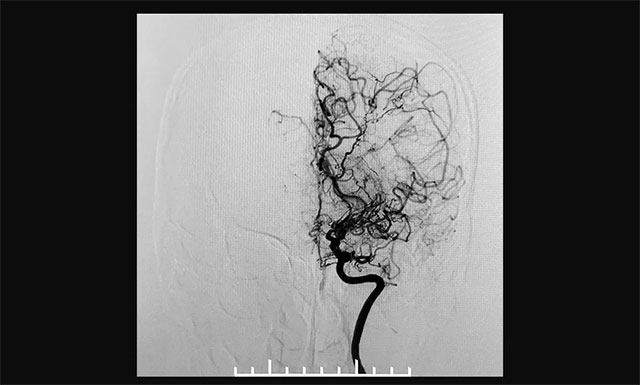

患者頭顱CTA示,左側(cè)大腦后動脈P1段偏細(xì),相應(yīng)左側(cè)后交通代償性增粗。DSA檢查顯示雙側(cè)頸內(nèi)動脈閉塞,可見異常血管形成,右側(cè)頸內(nèi)動脈未向顱內(nèi)供血,右側(cè)大腦后動脈通過皮層軟膜血管向右側(cè)大腦前、中動脈代償。既往有“高血壓”病史6年,收縮壓最高為180毫米汞柱,平時血壓控制欠佳。結(jié)合病史患者確診為煙霧病。

▲ 術(shù)前造影顯示,患者雙側(cè)頸內(nèi)動脈末端閉塞,顱內(nèi)煙霧狀血管形成